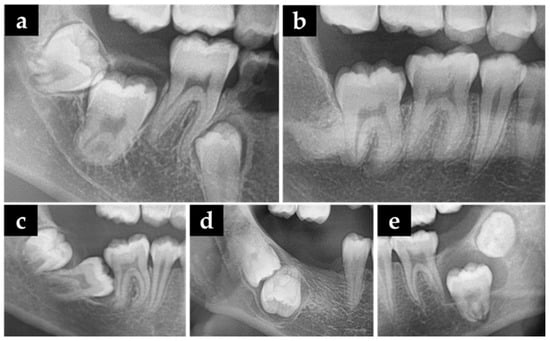

| Item/Impaction Type | Type I | Type II | Type III | Total | p-Value |

|---|---|---|---|---|---|

| Number of patients (n) | 39 | 25 | 31 | 95 | |

| Number of MM2 (n) | 63 | 38 | 36 | 137 | |

| Depth of mesial (mm, mean) | 5.63 ± 3.20 | 8.26 ± 3.45 | 12.16 ± 4.20 | 8.05 ± 4.42 | <0.001 ** |

| Depth of distal (mm, mean) | 0.55 ± 3.09 | 4.40 ± 2.78 | 9.70 ± 3.40 | 3.98 ± 4.84 | <0.001 ** |

| Risk factor (n) | <0.001 ** | ||||

| Insufficient space | 60 | 37 | 18 | 115 | |

| Ectopic eruption path | 3 | 0 | 7 | 10 | |

| Cysts of jaw | 0 | 1 | 11 | 12 | |

| Undercut (n) | <0.001 ** | ||||

| Undercut | 62 | 36 | 20 | 118 | |

| No-undercut | 1 | 2 | 16 | 19 | |

| Angulation (n) | <0.001 ** | ||||

| Horizontal | 7 | 6 | 6 | 19 | |

| Mesioangular | 55 | 30 | 17 | 102 | |

| Vertical | 0 | 1 | 5 | 6 | |

| Distoangular | 1 | 1 | 5 | 7 | |

| Other | 0 | 0 | 3 | 3 | |